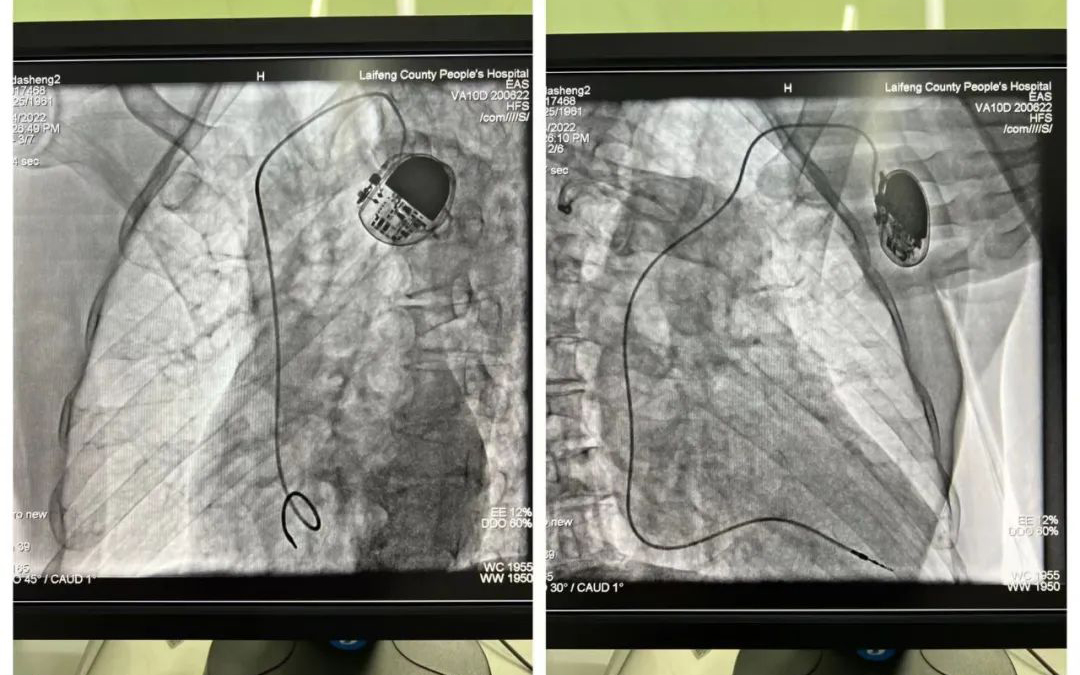

7月24日,我院成功开展了首例永久性人工心脏起搏器植入术,实现了我院在该领域“零”的突破。

为保证患者安全、手术顺利进行,我院心血管内科团队经过充分的术前讨论,认真分析患者的病情,并就手术细节等相关事项进行了仔细分析和研究,制定了详细周密的手术方案。7月24日上午11时,在恩施慧宜医疗集团张宏伟教授、我院副院长张承中及心内科副主任朱兴彪主治医师带领下,医护团队默契配合、细致操作,历时95分钟,我院首例永久性单腔心脏起搏器植入术顺利完成。术后,起搏器工作正常,患者感觉良好。